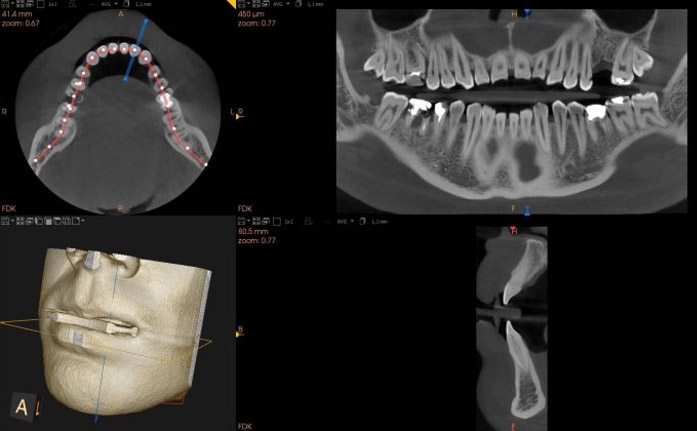

Tomografia komputerowa jest to badanie, które daje możliwość analizy wybranego fragmentu uzębienia wraz z tkanką kostną w formacie trójwymiarowym. Precyzja obrazu tomograficznego dostarcza ogromu informacji o morfologii danego obszaru i uwidacznia rozległość zmian chorobowych, dzięki czemu zabiegi lecznicze przeprowadzane są z pełną świadomością, sprawnie i przy zminimalizowaniu ryzyka niepowodzenia.

Tomografia głowy stała się niezbędna podczas wykonania procedur implantologicznych, chirurgicznych i w leczeniu kanałowym, wykonywanymi w Exclusive Dental Studio. Przejście ze zdjęć dwuwymiarowych na badania trójwymiarowe zrewolucjonizowało możliwości diagnostyczne i terapeutyczne we współczesnej stomatologii.

Dzięki postępowi technologicznemu w radiologii stomatologicznej dawki promieniowania w przeprowadzanych nawet najbardziej wymagających badaniach tomografem komputerowym zostały ograniczone do absolutnego minimum. W związku z tym pacjent nie musi obawiać się diagnostyki radiologicznej. Dodatkowo używając aparatu Carestream CS 9600 jesteśmy w stanie bardzo precyzyjnie określić zakres badania tomograficznego szczęki począwszy od jednego, konkretnego zęba (mikrotomografia) do obu łuków zębowych podczas jednej projekcji.